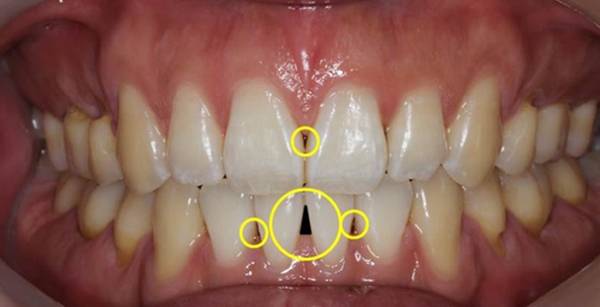

잇몸 양이 줄어드는 것을 알 수 있는 지표가 있는데, 바로 잇몸의 빈 공간인 '블랙트라이앵글'<사진> 이다. 사진>

잇몸 양이 줄어드는 것을 알 수 있는 지표가 있는데, 바로 잇몸의 빈 공간인 '블랙트라이앵글'<사진>이다. 약간의 블랙트라이앵글이 보인다면 꼼꼼한 칫솔질과 잇몸 관리를 철처히 해야 한다.

먼저 잇몸 염증을 주의해야 한다. 치태나 치석에 의해 잇몸에 염증이 발생하면 잇몸이 퇴축되면서 블랙트라이앵글이 만들어질 수 있다. 젊을 때보다 치아가 길어 보이는 것도 잇몸 염증으로 잇몸이 뿌리 쪽으로 올라가면서 치아의 치경부가 드러났기 때문이다. 이 경우 가벼운 양치질에도 잇몸에서 피가 나거나 잇몸이 시리고 붓는 등 증상이 나타날 수 있다.

특히 흡연은 블랙트라이앵글이 생기는 가장 큰 원인으로 꼽힌다. 흡연은 잇몸 건강을 악화시켜 치아를 지지하지 못하게 한다. 또한 치아를 깨끗하게 닦는다며 너무 힘을 주어 뿌리 부위를 세게 문지르는 잘못된 습관도 잇몸을 상하게 만드는 요인이다. 충치 치료를 한 후 치아를 씌운 크라운이나 보철물이 치아와 맞지 않거나, 시간이 지나 보철물과 치아 사이의 빈틈이 생기면 그 사이에서 세균이 번식해 잇몸이 손상될 수 있어 주의해야 한다.

한편, 스케일링 후에 블랙트라이앵글이 보이는 경우도 있다. 없던 블랙트라이앵글이 생긴 것이 아니라 치석을 제거하면서 감춰졌던 블랙트라이앵글이 드러난 것이다. 치석은 아래 앞니의 안쪽에 붙어있는 경우가 많은데, 치석이 자리잡은 공간은 점점 커지면서 그 부위의 잇몸을 밀어내버리고 서서히 없어진 잇몸은 치석을 제거해도 원래 모양대로 다시 차오르는 경우가 드물다. 심미적인 이유 때문이 아니라도 블랙트라이앵글이 크게 생긴 치아 사이는 음식물이 쉽게 끼게 되고, 치아의 뿌리가 드러나게 되면 이 부위는 찬물이나 짠 음식에 시리거나 충치에도 매우 약해지게 되므로 블랙트라이앵글이 보이기 시작한다면 치과에서 원인을 찾아 치료하는 것이 중요하다. 틈을 메우는 수복 치료를 받는 것이 구강 위생 관리에 도움이 될 수 있다.